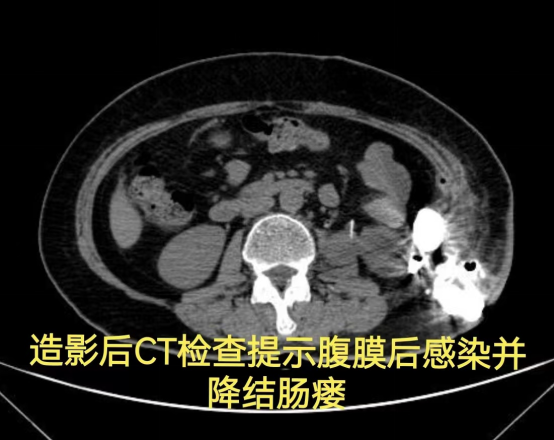

病情简述:56 岁女性,两次腹膜后手术后出现降结肠瘘。

诊疗破局: 按传统疗法,需先做结肠造口(挂粪袋),等半年后再做二次手术还纳。为减轻患者痛苦,团队制定「清创、控感、一期修复」三步法,实施腹腔镜下瘘切除+一期结肠端端吻合术。术后一周患者正常进食,免去了半年造口之苦。

技术体现: 精准的术前评估与微创技术,让创伤最小化与疗效最大化不再是单选题。